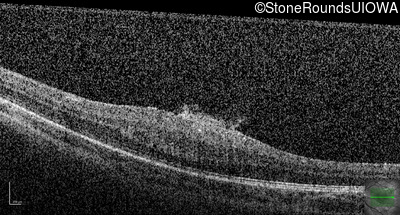

This 9 year old male was noted to have some crossing of his eyes at 2 months of age and the eye exam which followed identified a retinal lesion in the right eye. When he was six years old an epiretinal membrane was noted in his left eye. Two years later it was decided that it was a thin hamartoma in that eye as well. He underwent neuroimaging at age 7 which identified bilateral acoustic neuromas.

| Age at visit: 8 years |